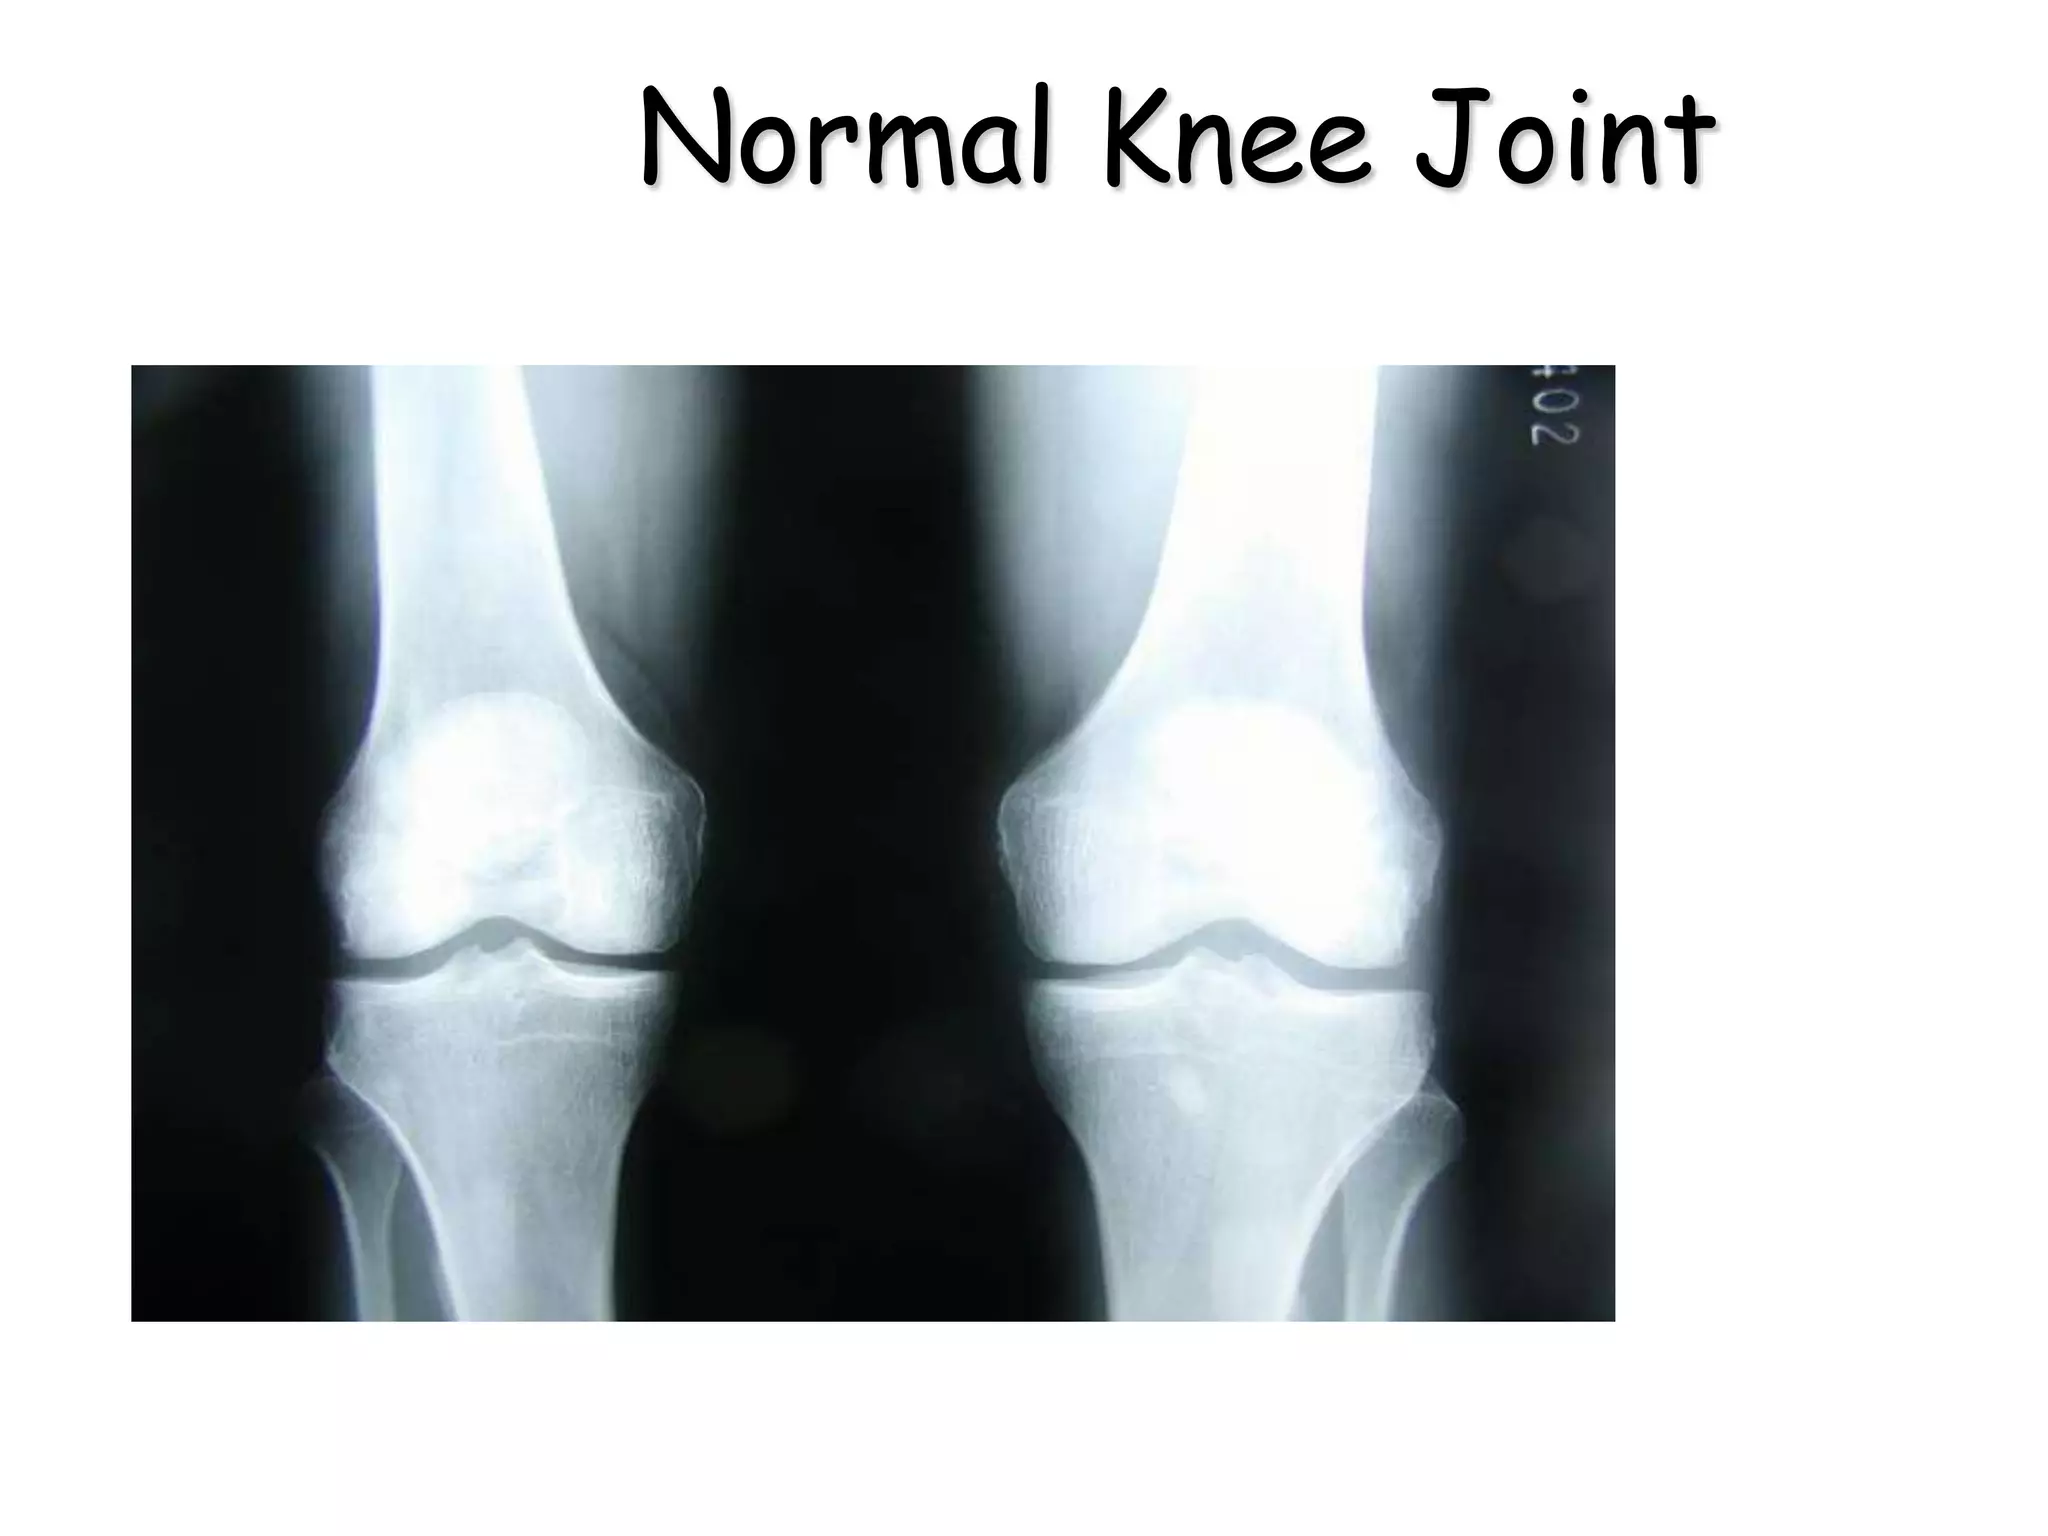

•X-rays do not show cartilage.

•In a normal joint a gap is seen

between the bones.

•In Osteoarthritis this gap between

the bones gradually diminishes and

disappears.

What will X-rays show ?

Normal Knee Joint